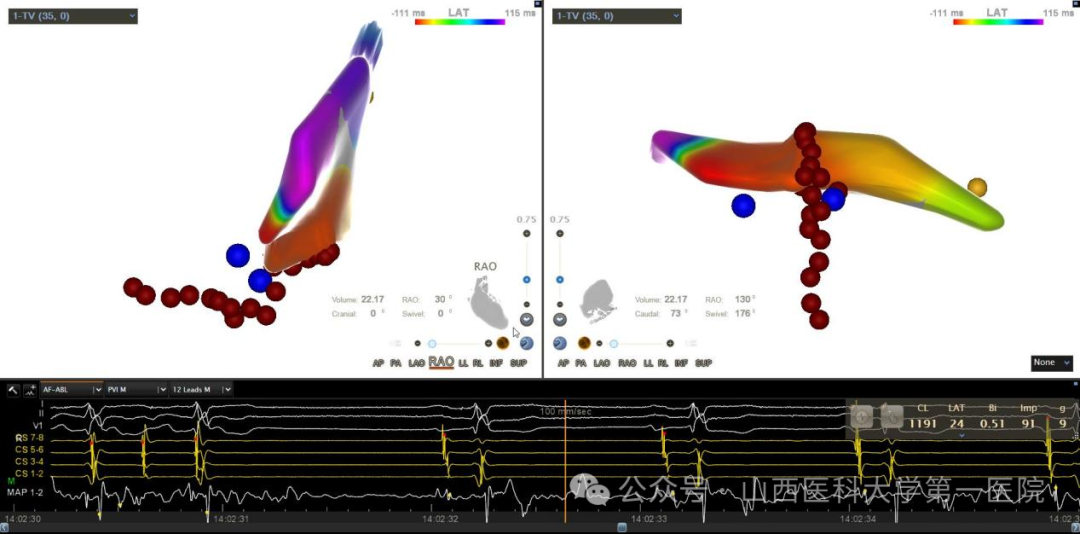

次日,通过超声影像科经食道超声再次精确评估,明确患者房缺缺损直径达37mm,肺动脉压65mmHg。一般临床中通过介入封堵的最大房缺为36mm以下,否则需要外科开胸来进行房缺修补,但患者心衰症状刚刚改善,身体整体状态欠佳,患者及家属对开胸手术存在很大顾虑。电生理团队经过评估后认为患者虽然巨大房缺,但各残缘情况尚可,存在介入封堵的可能,并结合技术优势可以在心腔内超声辅助下指导封堵伞的释放,再次与患者及家属沟通后决定采用射频消融+房缺介入封堵一站式微创手术方案,王睿主任医师团队顶着高难度高风险的压力为患者实施了三维标测下房扑射频消融术+房间隔缺损封堵术。术中,在可调弯长鞘的辅助下精细标测确定患者房扑为围绕三尖瓣峡部折返的典型房扑,三尖瓣峡部电隔离后患者房扑终止,恢复窦性心律;接下来,在心腔内超声指导下,选择42mm大封堵伞进行精确释放,成功封堵巨大房缺。封堵前后患者血氧明显改善,肺动脉压无进一步升高,观察二十分钟,患者无不适,反复牵拉实验示封堵伞位置稳定,遂释放封堵伞,完成手术。术后第三天复查心脏超声,显示封堵器位置固定,未见穿隔分流。